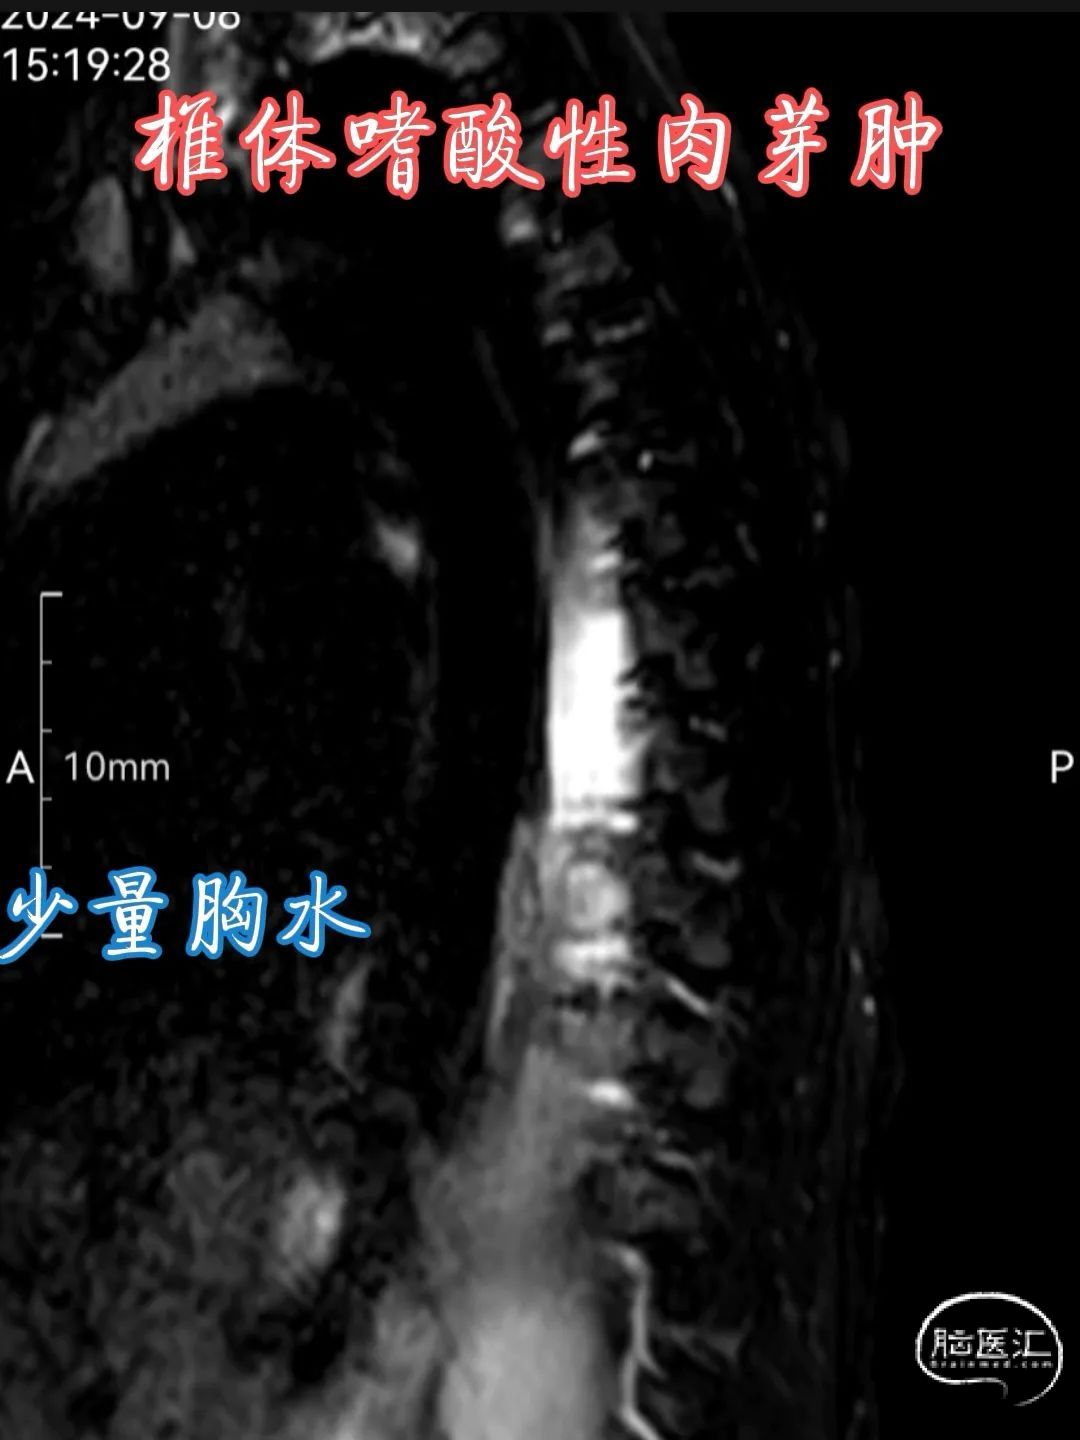

•MRI 检查 :MRI 对于检测椎体嗜酸性肉芽肿具有较高的敏感性,能够清晰地显示病变的范围、部位、形态以及与周围组织的关系。在 T1 加权像上,病变通常呈低到中等信号强度,与正常骨髓相比信号较低;在 T2 加权像上则呈高信号强度,这是由于病变组织内含有较多的水分和黏多糖等成分。此外,MRI 还可显示病变周围的软组织水肿、炎症反应以及神经受压等情况,对于判断病情和制定治疗计划具有重要价值。